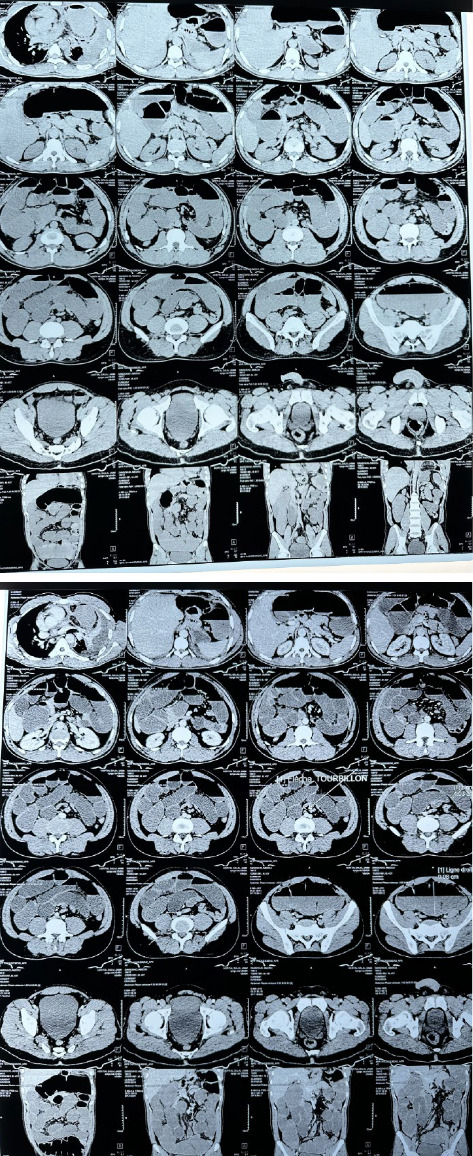

创伤后膈疝(PTDH)被定义为由创伤引起的膈病理缺损引起的腹内器官向胸腔内迁移。PTDH是一种罕见的疾病,发生在所有胸腹损伤的3%-7%。大约14.6%的PTDH病例在初次创伤后数月至数年出现。延迟PTDH并发肠梗阻和穿孔的病例极为罕见,据报道患病率为0.17%-6%。在非洲,在过去三十年中记录的延迟PTDH病例不到10例。尽管有已发表的报告,但目前尚无管理PTDH的既定实践指南。在这里,我们提出一个延迟PTDH的情况下,表现为急性肠梗阻12年后枪伤到胸部。这种情况导致了致命的术后结果。本病例强调了临床医生在有创伤史的急性肠梗阻患者中考虑PTDH的迫切需要,并强调了紧急手术治疗以防止致命并发症的重要性。

Post-traumatic diaphragmatic hernia (PTDH) is defined as the migration of intra-abdominal organs into the chest through a pathological defect in the diaphragm caused by trauma. PTDH is a rare condition, occurring in 3%-7% of all thoracoabdominal injuries. Approximately 14.6% of PTDH cases present months to years after the initial trauma. Cases of delayed PTDH complicated by bowel obstruction and perforation are exceedingly uncommon, with a reported prevalence of 0.17%-6%. In Africa, fewer than 10 cases of delayed PTDH have been documented over the past three decades. Despite the availability of published reports, there are no established practice guidelines for managing PTDH. Here, we present a case of delayed PTDH that manifested as acute bowel obstruction 12 years after a gunshot wound to the chest. The condition led to a fatal postoperative outcome. This case highlights the critical need for clinicians to consider PTDH in patients with a history of trauma presenting with acute bowel obstruction and underscores the importance of urgent surgical management to prevent fatal complications.